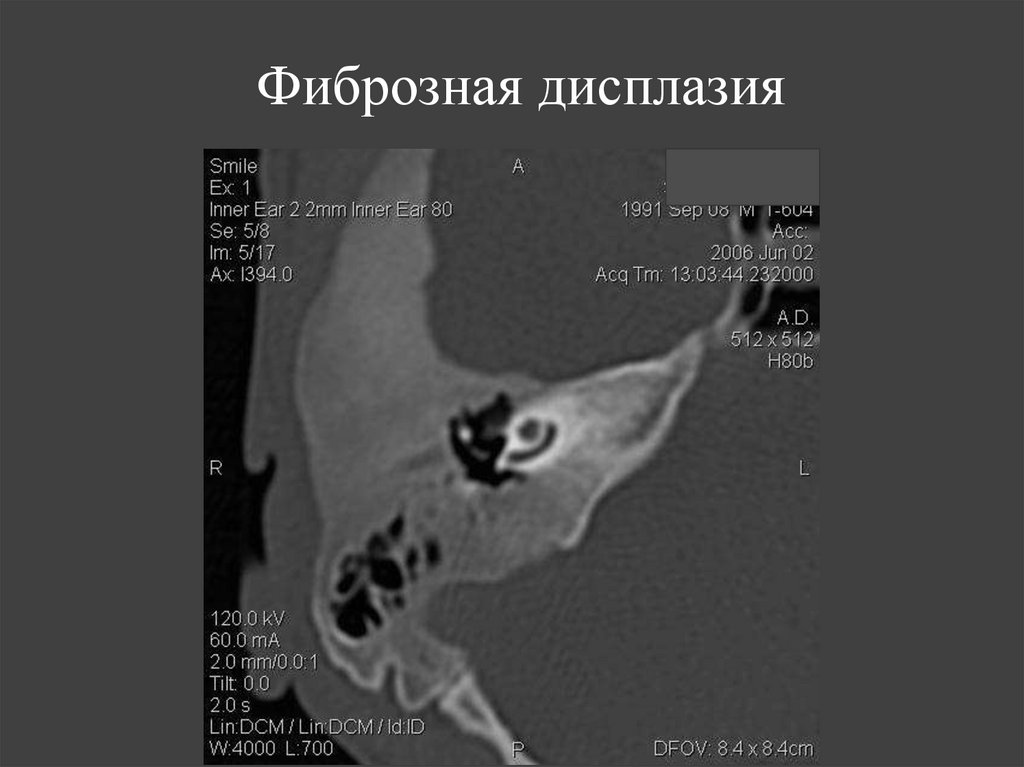

127. Фиброзная дисплазия

128.